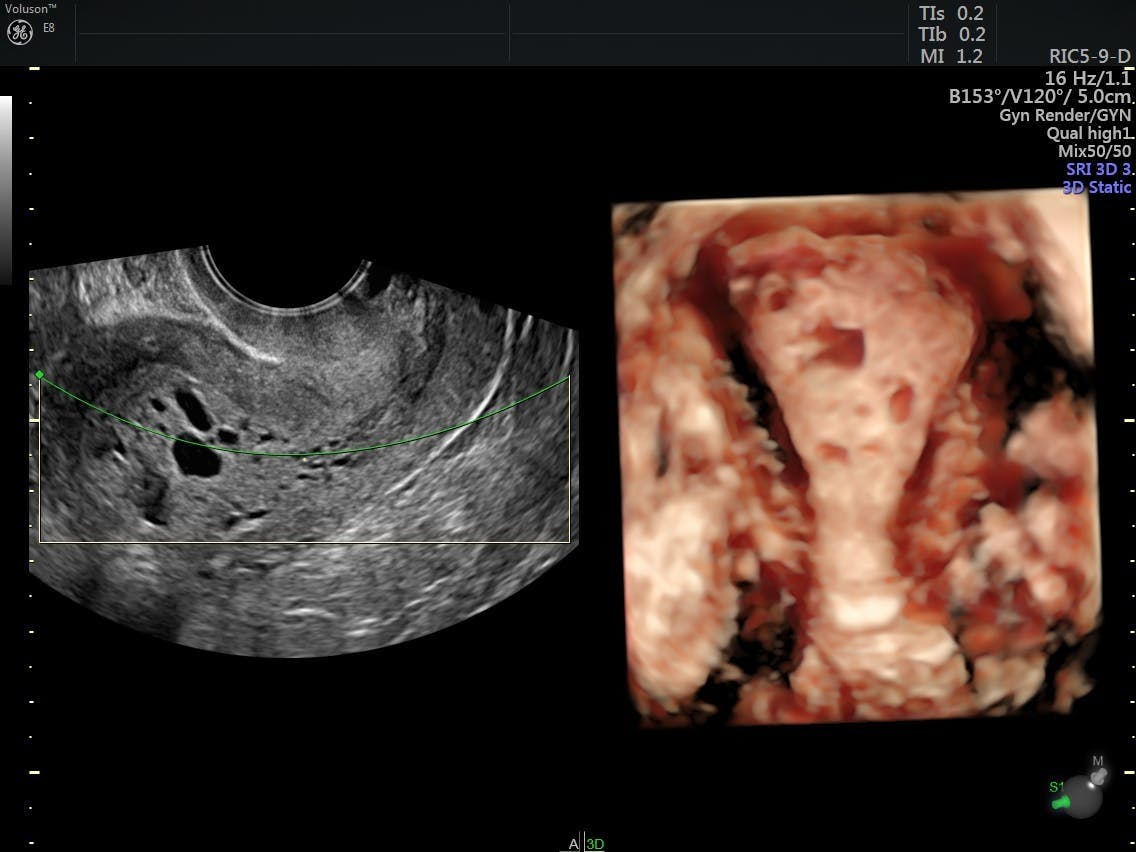

Case 1 Endometrial Hyperplasia Transvaginal Ultrasonography At Download Scientific Diagram

Endometrial Hyperplasia Collection Of Ultrasound Images